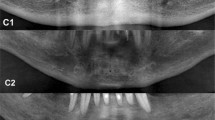

Mandibular cortical index (MCI, qualitative parameter): morphological appearance of the mandibular cortical bone distally to the mental foramen by bilateral inspection; “C1” represents normal cortex, “C2” moderately eroded cortex, and “C3” severely eroded cortex [13] (Fig. 1).

The results of the qualitative inter-group comparisons are summarized in Figs. 4, 5. Regarding the MCI, statistically significant differences within the experimental dialyzing group and healthy control group (p < 0.001) could be found. In the dialyzing group N = 10 (24.4%) men showed a normal cortex structure, N = 25 (61.0%) men a moderately eroded cortex, and N = 6 (14.6%) patients a severely eroded mandibular cortex structure. In the healthy control group, in N = 33 (80.5%) patients a normal cortical structure and in N = 8 (19.5%) men a moderately eroded cortex structure could be detected (Fig. 4).